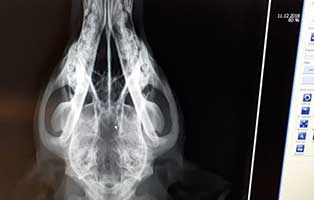

Der junge Hund ist ca. ein Jahr alt, wir vermuten, dass sie irgendwo in einem Hinterhof aufgewachsen ist. Vielleicht sollte sie als Welpe verkauft werden und niemand kaufte sie. Möglicherweise ist sie deshalb total unsozialisiert, auch mit anderen Hunden. Heute waren wir beim Tierarzt und haben sie röntgen lassen und ein Blutbild wurde gemacht. Auf dem Röntgenbild war aber nichts zu sehen, deshalb muss Luna in eine Klinik und ein CT muss gemacht werden. Irgendwie müssen wir die Ursache für die neurologischen Störungen finden um aus Luna einen glücklichen Hund machen zu können.

Luna die Fundhündin in der Klinik, warten auf MRT, ursprünglich CT, Doktor hält MRT für angebrachter. Daumen drücken. Ihr Zustand hat sich in den letzten Tage verschlechtert.

Es gibt Tage da gewinnt man, und es gibt Tage da verliert man. Gestern war der Tag, wo wir verloren haben. Eine bittere Niederlage gegen eine unaufhaltsame Krankheit. Das MRT zeigte leider Bilder, die keinen Zweifel daran ließen, dass wir uns von Luna verabschieden mussten. Sie hatte eine Hirnatrophie im fortgeschrittenen Stadium. Und da sich ihr Zustand die letzten Tage sehr verschlechtert hatte, haben wir uns dazu entschieden, sie nicht mehr aus der Narkose aufwachen zu lassen. Sie hatte keine Lebensqualität mehr. Lief fast 24 Stunden ununterbrochen Kreise und kam nicht mehr zur Ruhe. Leider gibt es für diese Krankheit keine Aussicht auf Besserung oder gar Heilung. Wir werden wohl nie erfahren, wo sie herkam, was sie erlebt hat und warum sich niemand für sie meldete. Sie schlief ganz ruhig in den Armen ihrer Tierpflegerin ein. Machs gut Luna, nun kannst du in Ruhe schlafen.